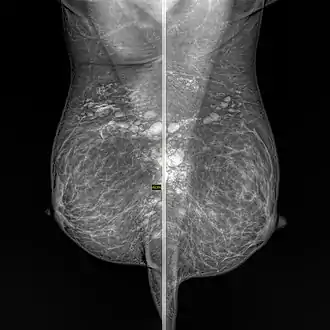

Silicone granuloma